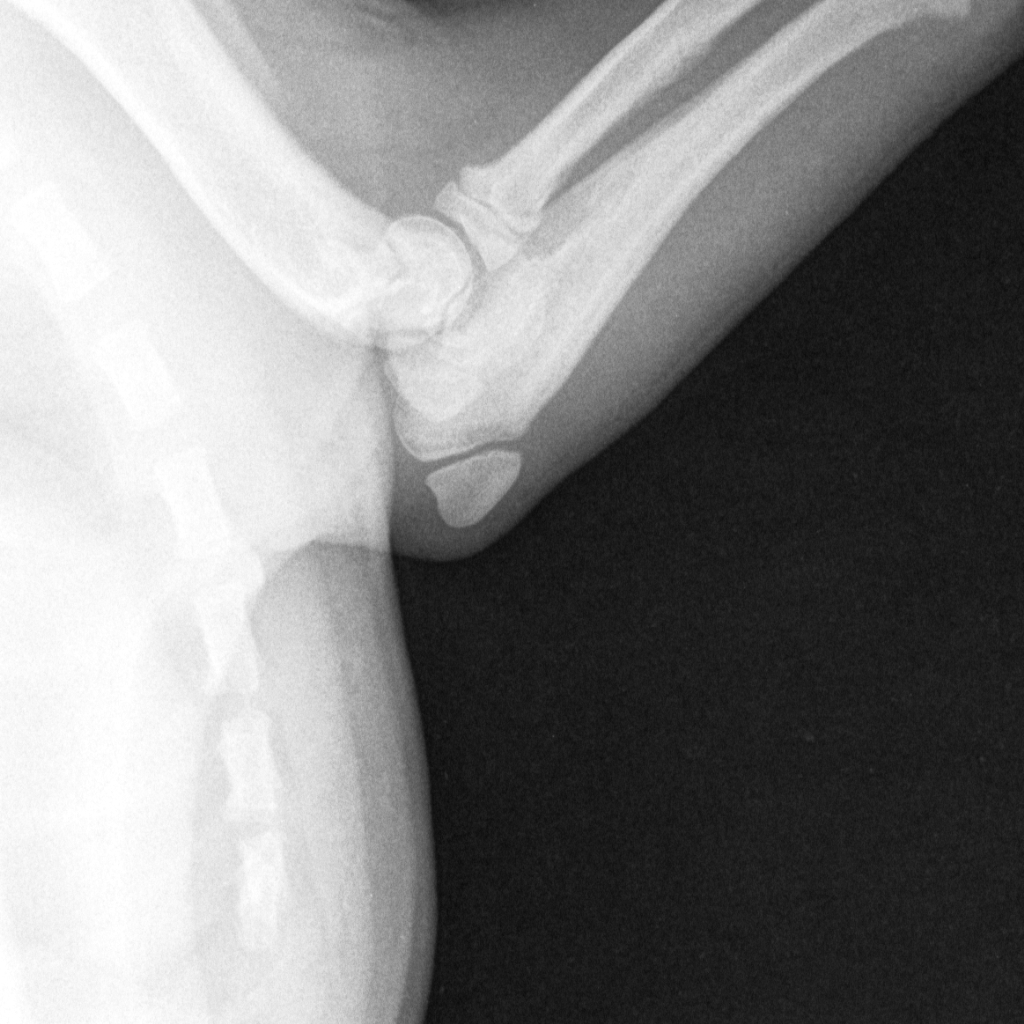

An X-ray of Tony's injury

Tony, who was among a litter of puppies bred by Brown in September last year, was suffering from a swollen left elbow and x-rays confirmed a fracture. On January 3 this year he underwent a three-hour long operation and in a vet’s expert opinion the extended time under anaesthetic posed a greater risk to the canine because of his brachycephalic breed.

A vet’s report presented to the court stated the surgeon described Tony’s fracture as chronic and said the outcome to the surgery would have been far better had the operation been done in the first two to three days after he was injured - something his owner failed to provide.